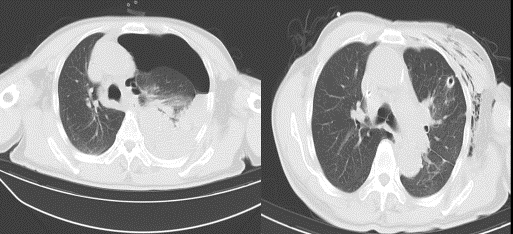

2、CT检查能显示大疱的大小,有助于与气胸的鉴别诊断。03

肺大疱患者应定期进行胸部X线、CT等影像学检查,以监测病情变化和治疗效果。同时,注意观察症状变化,如有不适及时就医。